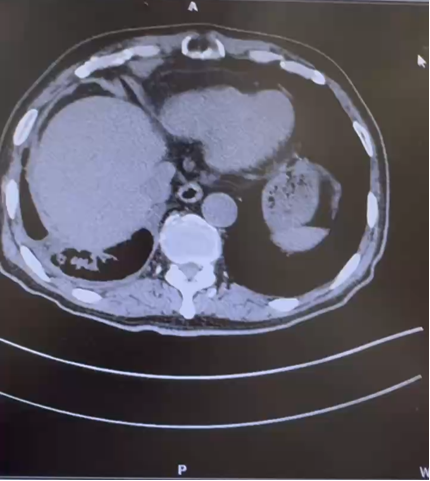

CT(2022.1):1. 左肾肿块,肾癌并出血可能;2. 左输尿管上段结石并周围炎症,左肾结石并积水;3. 右肾萎缩;4. 肝囊肿。

2022.1 靶免联合新辅助治疗

新辅助治疗前

新辅助治疗后

治疗后复查 CT(2022.7):左肾透明细胞 CA 治疗后改变,肿块较前缩小,强化程度减低,左侧副肾动脉可见;余况同前。